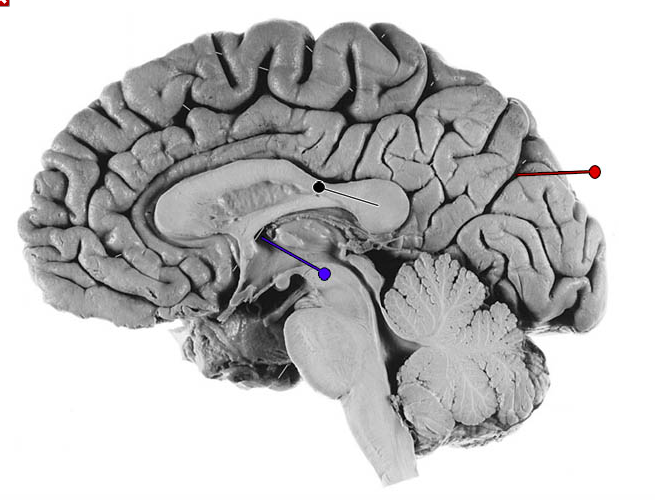

What is the structure indicated by the black pin?

?

What fibres is the structure marked by the black pin made up of?

Commisural fibres